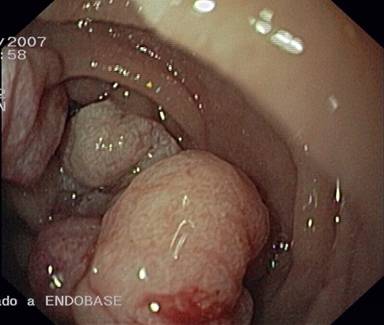

A 67-year-old woman with a body mass index of 40 Kg/m2 was admitted to our hospital complaining of acute upper gastrointestinal bleeding. She had experienced a syncope episode followed by melenas. An upper digestive endoscopy revealed a large friable polypoid mass about 5 cm in diameter, surrounding 3/4 of the internal lumen, coming from the 3rd portion of the duodenum, about 3 cm distal to the ampulla (Figure 1). There were no other polypoid lesions in the duodenum. Multiple endoscopic biopsies (five samples) confirmed a villous adenomatous polyp with mild-moderate dysplasia. Abdominal CT showed the mass to be confined to the duodenum. An extension study was completed via endoscopic ultrasonography which showed no disruption of any of the muscle layers of the duodenum (Figure 2) and no penetration into the pancreas. The pancreatic duct was preserved and there were no pathological regional lymph nodes. Tumor markers (CEA and CA 19-9) were negative. From the day of admission to the day of the surgery, the patient required transfusion of 7 units of red blood cells.

Figure 1. Duodenoscopy revealing a large polypoid mass. |